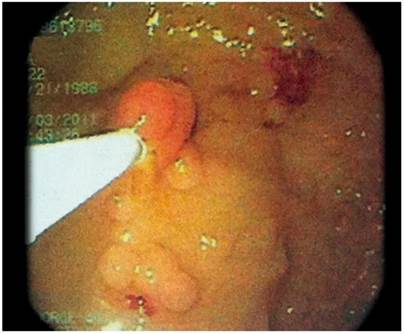

A complete blood count and blood chemistry were normal. In addition, barium enema abdominal radiography found alterations of the colonic frame with accumulation of secretion (Figure 1). In the rectosigmoidoscopy, more than 100 polyps of sizes ranging from 3 mm to 5 cm were observed from the distal ascending colon to the rectum. Some were pediculate and others were sessile, tubular and villous in appearance (Figures 2 and 3).

The histopathological study shown in Figure 4 reported that:

The mucosa of the sigmoid colon had tubular adenoma with high grade focal dysplasia (10%).

There were tubular villous polyps in the transverse colon polyps and adenoma with a predominance of the adenomatous component in 80% of the material examined plus areas of high grade focal dysplasia.